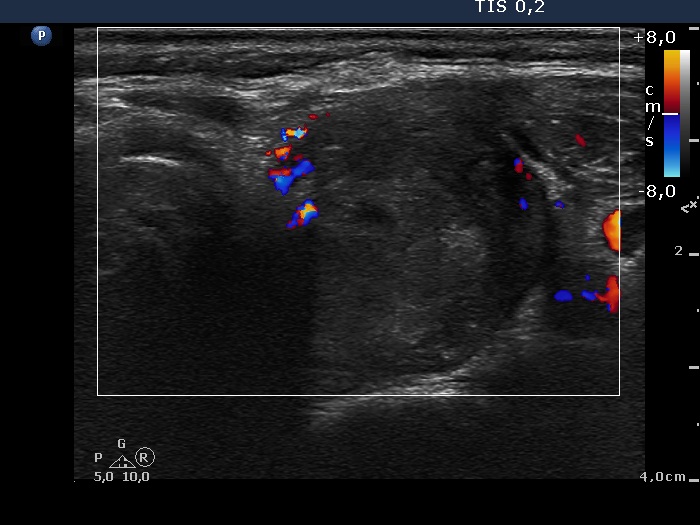

Follow-up investigation 11 months after the initial one (ultrasonographic picture 7)

Upper part of the left lobe, transverse scan, color Doppler mode. The vascular pattern of the nodule remained unchanged.